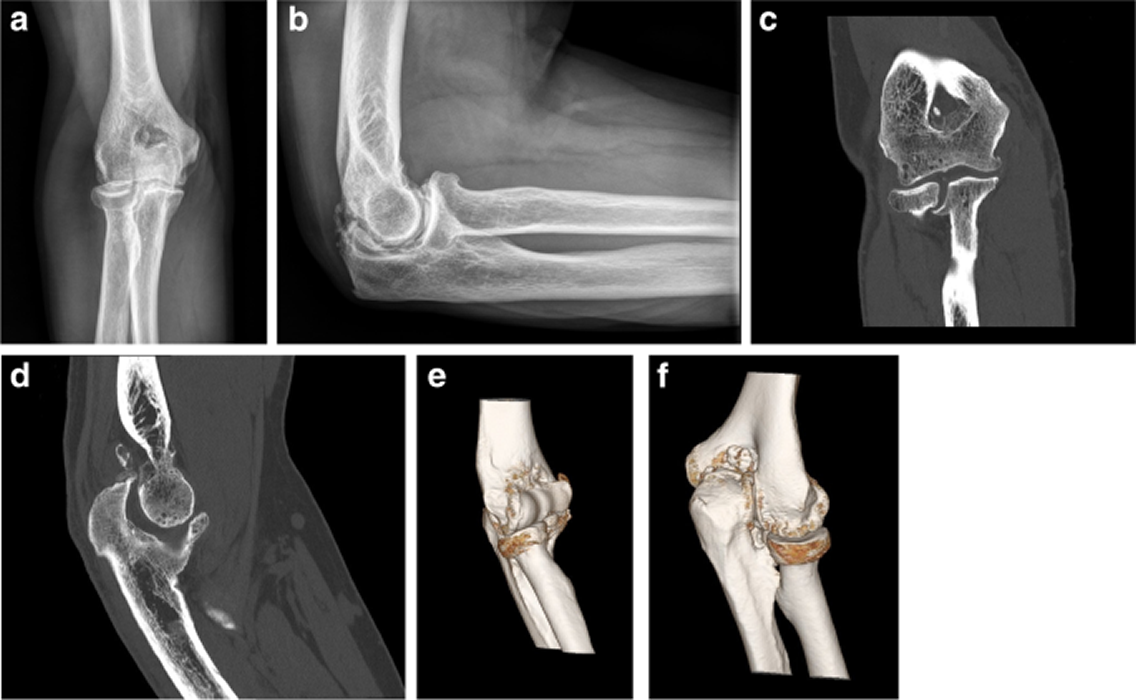

Διάγνωση

Η εκτίμηση γίνεται από τον ορθοπεδικό και μπορεί να περιλαμβάνει:

• Κλινική εξέταση για τον έλεγχο της κίνησης

• Ακτινογραφίες ή μαγνητική τομογραφία για ανίχνευση βλαβών ή εμποδίων στην άρθρωση